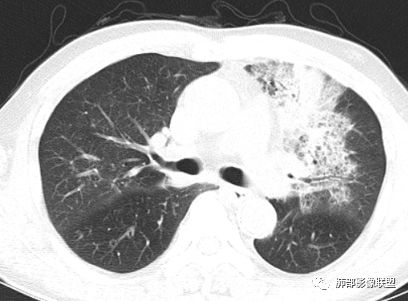

胸CT:左肺上叶前段实变,其周围及左肺上叶尖后段可见肺气肿背景下渗出性病变,病灶内可见支气管扩张,气道壁呈不规则增厚,双肺散在小结节状影;右肺下叶结节影,内可见空泡,边缘模糊,不规则。增强可见病灶内血管造影征,右肺门增大,纵隔淋巴结多发肿大。

左肺上叶大片混合网格磨玻璃影,边界清,边缘分叶膨隆,内支气管走行狭窄扩张,实变区边界清,上叶支气管管腔窄,心膈角淋巴结肿大,考虑肺炎型肺癌—腺癌。左肺下肺门结节,边缘膨隆,突入中间段及下叶支气管腔,背段支气管阻塞,周围少量小花小草,考虑鳞癌。右下叶外侧基底段结节,边缘有膨隆,有血管牵拉进入,上缘支气管贴边,考虑肺癌,性质?

薏米:老年男性,发热,咳嗽5天,胸痛2天,平素慢性咳嗽,咳痰10年,未系统诊治,基础糖尿病史,此次以急性发病为主,白细胞正常,CRP增高,IGE增高,CEA轻度增高,左肺上叶散在片状密度增高影,边界清楚,小叶间隔增厚,内有磨玻璃影,部分支气管壁增厚,部分有扩张,部分有近段粗细不均,少许气囊,右肺下叶可见一结节影,有凹陷,有膨隆,似有结节感,综合考虑左肺上叶考虑黏液性腺癌,鉴别曲霉,抗感染后复查:右肺下叶恶性。

老年男性,糖尿病病史,crp及ige明显增高,cea轻度增高。影像:左肺上叶前段网格状高密度影,部分实变,部分前段支气管走形僵直。右肺下叶背段近肺门处及右肺下叶外侧基底段各见一枚结节,可见浅分叶,外侧基底段结节可见空泡。纵隔多发淋巴结肿大。综合考虑:肺癌,粘液腺癌?

左肺上叶支气管壁增厚,管腔狭窄,相应上叶肺组织内见片状磨玻璃影,内见网格影,边缘不清。右肺下叶背段近肺门区结节,背段支气管变窄,后基底段结节,周围肺组织内散在片状影,边缘不清,膈肌上方,边缘毛糙,纵膈内多肿大淋巴结,伴钙化。肝病及糖尿病病史,考虑占位,鳞癌?建议支气管镜检查。鉴别诊断淀粉样变性?血管炎?

读有点难,一个急性起病的临床特点与影像显然不符;而影像很难用一元化都解释得通,多个叶段受累,主要沿支气管血管束分布,而不是沿胸膜外带分布,内部支扩直达底部,网格、囊,甚至囊内结节,实变、双肺多发结节,纵隔多发淋巴结肿大伴钙化,右肺下叶结节,细节不够,远心端似乎见支气管征象,引流区域淋巴结肿大,考虑既有淋巴增生又有气道分布特点,结核并有曲霉可能性较大,不除外淀粉样变;需要与恶性肿瘤鉴别包括淋巴瘤、腺癌。

左肺上叶病灶长轴与支气管走形一致,提示沿支气管分布病变,倾向于炎性,大家可能怀疑这个病例是来源于胸膜下为主的,胸膜下来源首先整体是来源于胸膜下,与胸膜下之间没有间隙,而这例与胸膜下有间隙。而且这个病变是沿支气管朝外蔓延的,而胸膜下来源的是朝内蔓延的,唯一给我们错觉的是靠近纵隔胸膜这个地方有问题。但是靠近纵隔胸膜这个位置实变不是靠近胸膜实变,它边缘收缩的,没有膨隆的迹象。我们看到里面支气管直达远端稍扩张,是以中央间质为主、小叶间隔朝外蔓延,有间质也有实质病变,走向是沿中央间质方向走的,我个人倾向炎性病变。    问题是右下叶病灶怎么解释?右隔上、右肺门各有一个结节。这个病人有急性咳嗽、胸痛的病史,还有糖尿病病史,周围渗出比较明显,应该警惕炎性病变,要警惕克雷伯杆菌、结核、金葡菌霉菌,因为糖尿病人经常好发这些病菌感染。那么右下叶病变怎么考虑?能不能一元论?    左肺病灶是一个急性渗出为主的病变,一个急性感染的迹象;右肺下叶背段结节,没有看到支气管,增强图支气管壁增厚,局部小结节,呈分叶状,支气管堵塞,没有粘液栓样指套样改变,但是里面有强化,我倾向于癌,其次待排结核。我还是倾向于癌的可能性,恶性可能性大一些,可惜我看不到支气管腔内。还考虑有没有淀粉样变性的问题,弥漫钙化灶最常见的一个是结核,另一个是淀粉样变性。叶段支气管壁有弥漫增厚的迹象。所以淀粉样变性跟结核都要考虑。